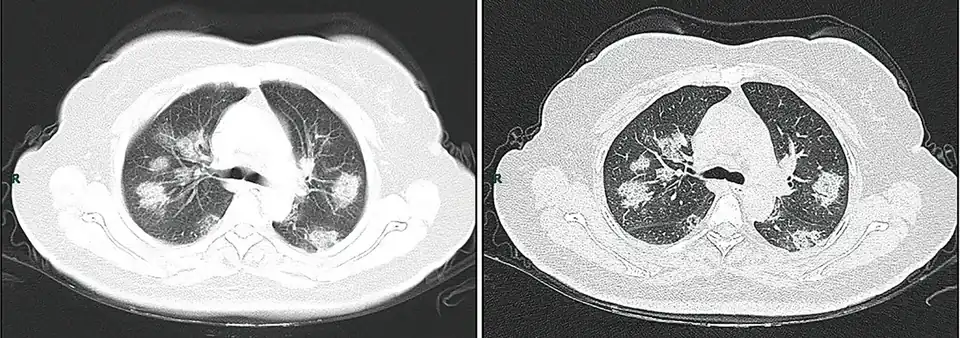

Radiologische tests

Met beeldvormend medisch onderzoek van de borstkas kunnen longafwijkingen gezien worden die mogelijk verband houden met COVID-19.

In een literatuuronderzoek van maart 2020 werd geconcludeerd dat "thoraxfoto's van de borstkas in een vroeg stadium van weinig diagnostische waarde zijn, terwijl CT-scans mogelijk al voor het begin van de symptomen het virus kunnen detecteren."[31][32]

Een studie waarin PCR wordt vergeleken met CT in Wuhan in het epicentrum van de huidige pandemie, heeft gesuggereerd dat CT significant gevoeliger is dan PCR, hoewel minder specifiek.[33]

Diagnose op grond van CT-scans is door zijn snelheid een goed alternatief voor PCR-test en heeft bovendien als voordeel dat ook de ernst van de ziekte in de longen is vast te stellen.[34]

Visuele analyse

Een kleinschalige studie toonde aan dat Chinese radiologen 72-94% gevoeligheid en 24-94% specificiteit toonden bij het differentiëren van COVID-19 van andere soorten virale longontsteking met behulp van CT-beeldvorming.[36]

Computeranalyse

Met behulp van kunstmatige intelligentie werd een hogere specificiteit bereikt.[37][38]

-

CT-scan van de borstkas van 38-jarige man met COVID-symptomen -

CT-scan van 50-jarige vrouw met COVID-symptomen